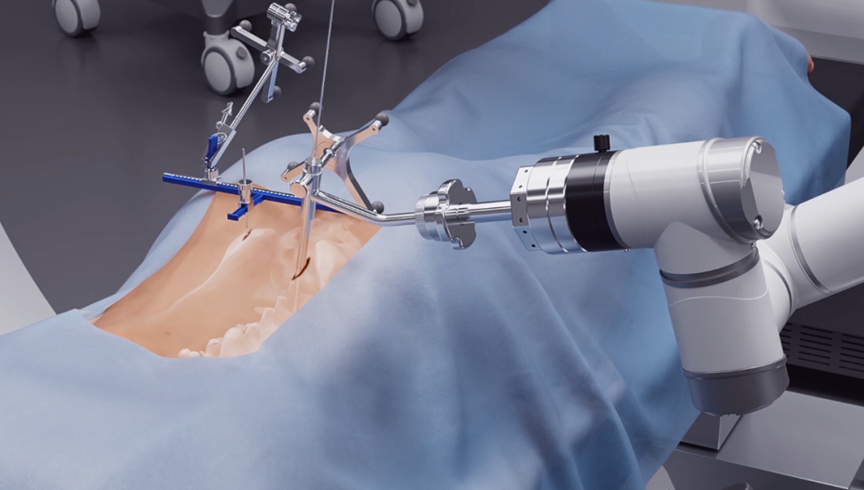

Recently, the orthopedic team at Children's Hospital of Nanjing Medical University successfully performed a scoliosis correction surgery for a 5-year-old girl with the assistance of the Perlove Medical’s orthopedic surgical robot. The surgery helped the young patient straighten her spine and stand tall again.

Children's Hospital of Nanjing Medical University successfully completed this highly complex surgical procedure through the integrated application of Perlove Medical's 3D C-arm and surgical robot, demonstrating optimal synergy between intelligent technology and surgical expertise.

01 Precision Navigation

During the surgery, the medical team used the Perlove Medical’s flat-panel 3D C-arm to acquire 3D and CT-like images of the patient, enabling comprehensive visualization of the pedicles. Guided by the robot's 3D planning system, the surgeon mapped each screw's ideal path and angle to achieve maximum screw purchase strength and improve spinal stability by accommodating the unique biomechanical properties of pediatric bone tissue.

One-time planning for quadruple K-wire insertion

The robotic arm enhanced stabilization of surgical instruments, enabling precise execution. Guided by pre-planned trajectories, the system achieved accurate single-attempt pedicle screw placement within narrow vertebral pedicles - effectively navigating the 'anatomical labyrinth'. This approach eliminated risks associated with repeated positioning attempts. The fully integrated system demonstrated perfect coordination, successfully completing the implantation of four pedicle screws with sub-millimeter accuracy.